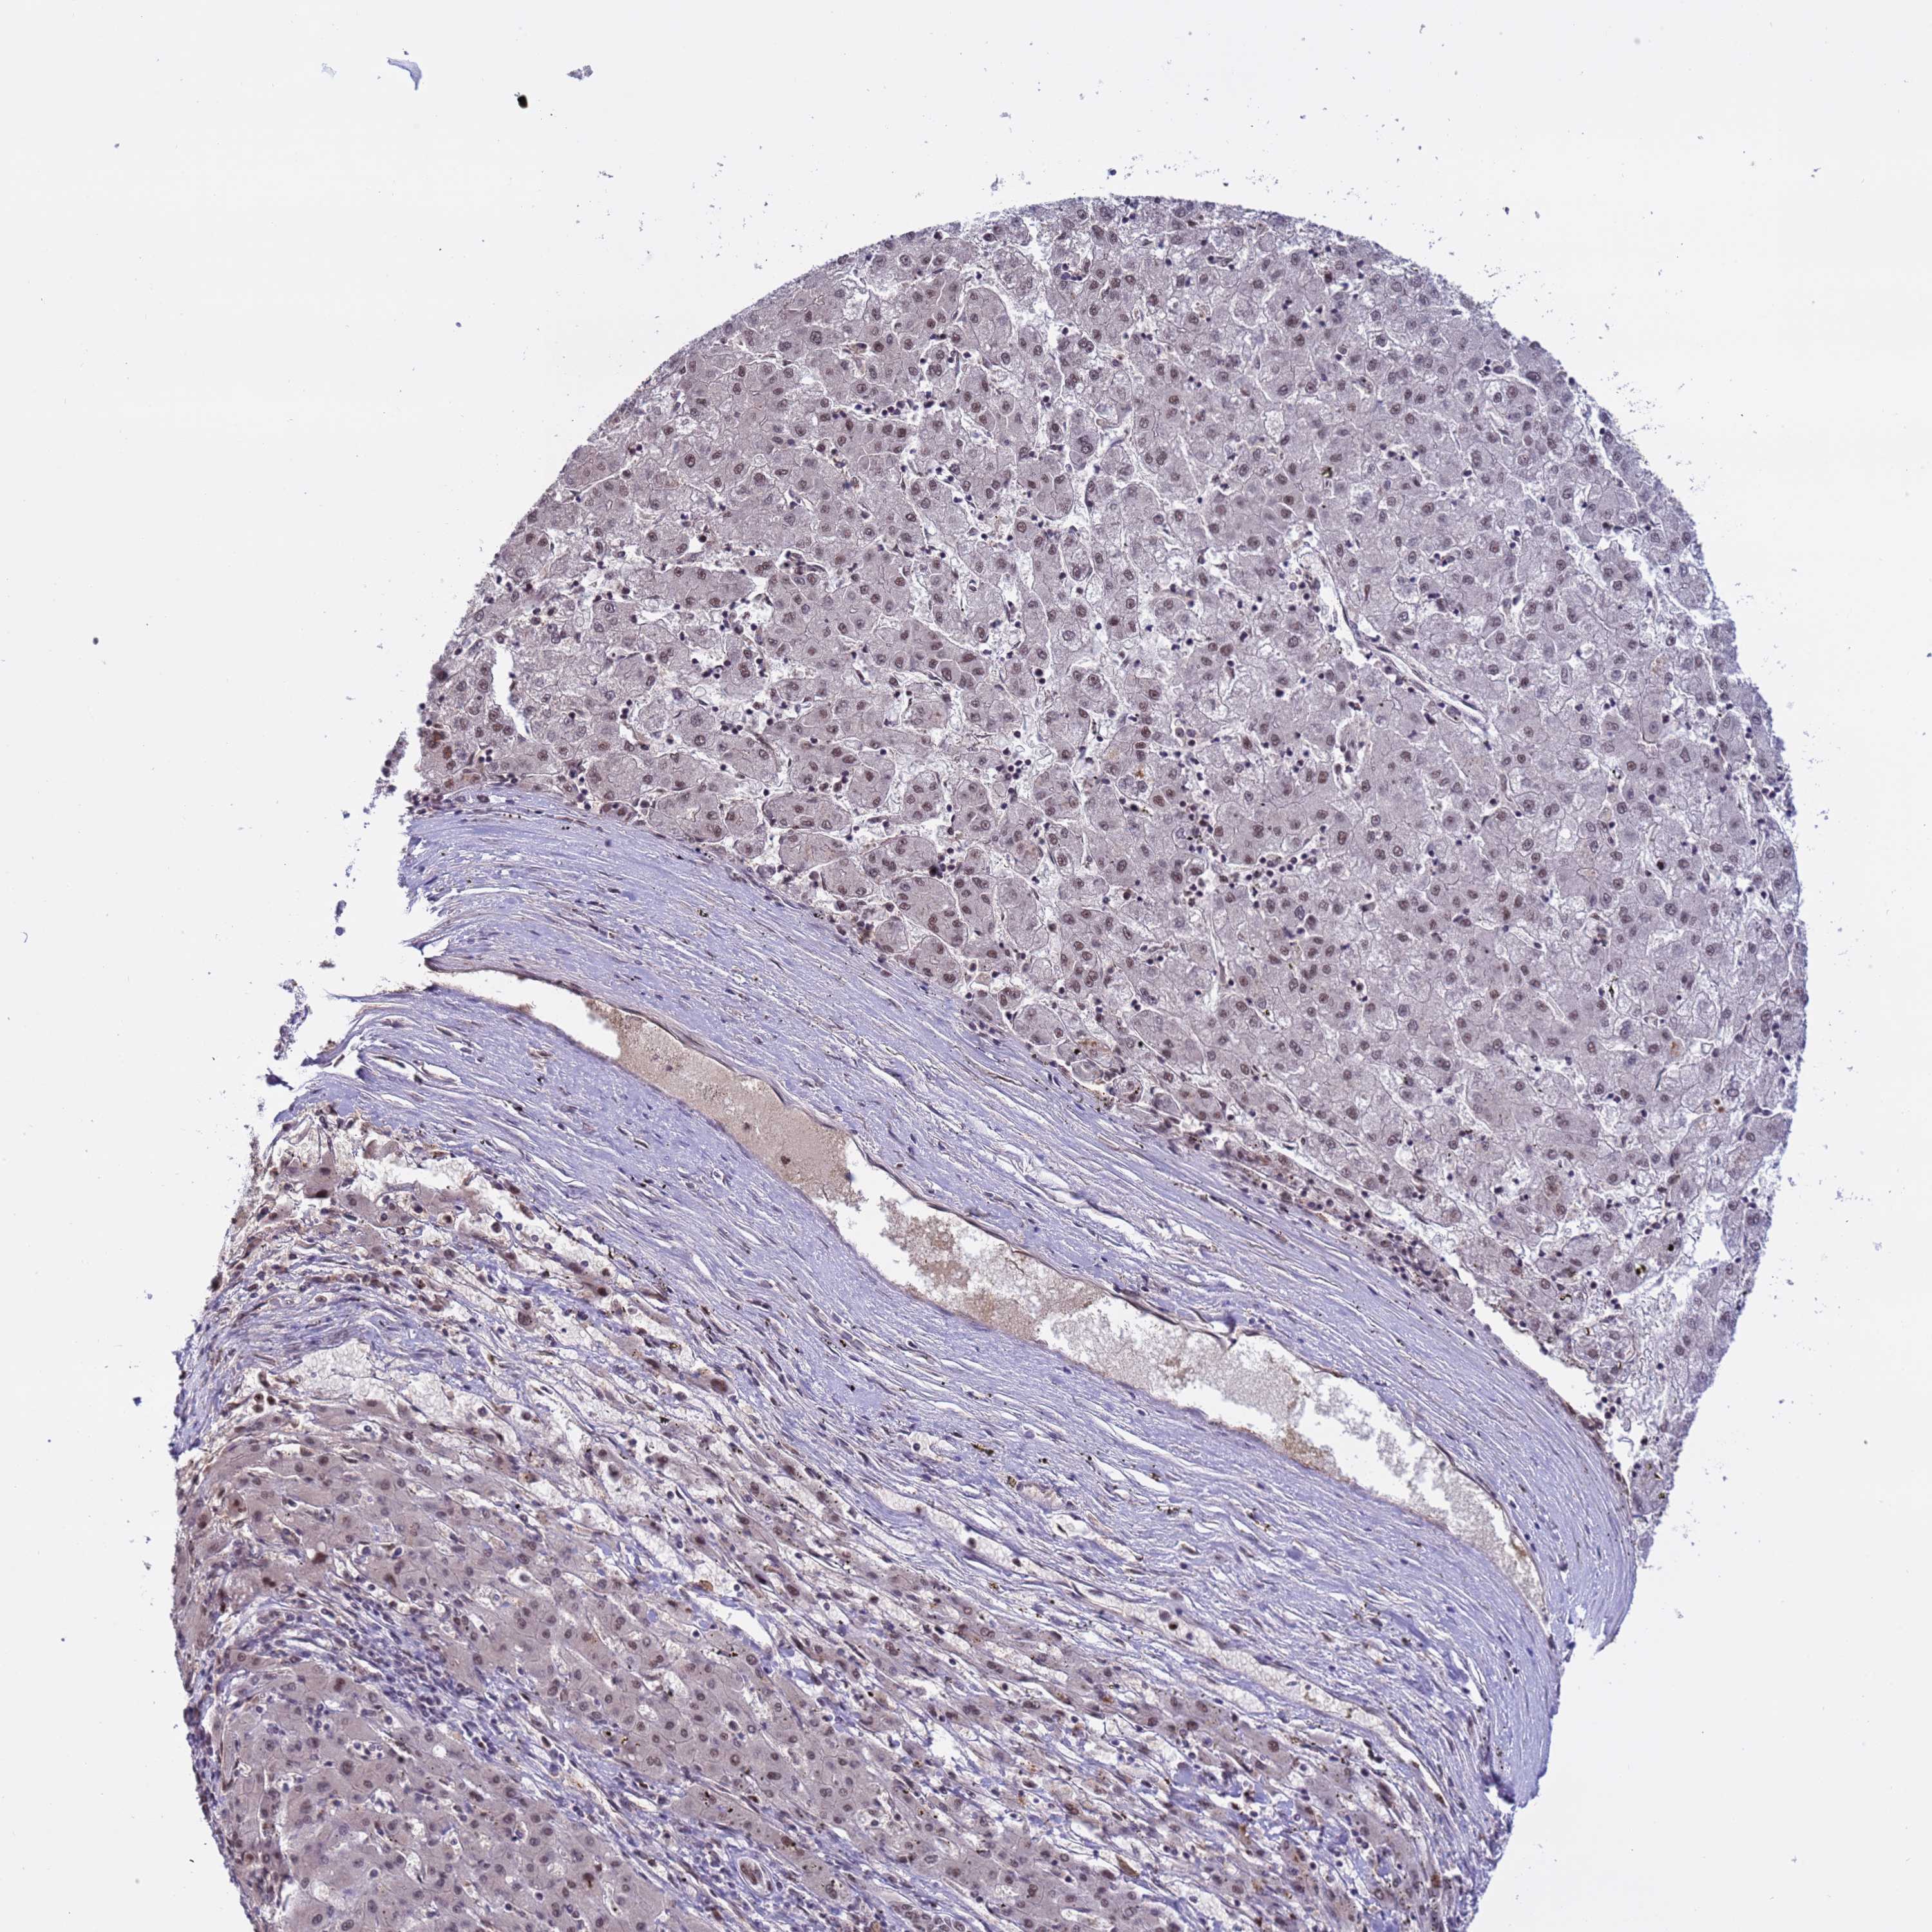

LIVER CANCER - Protein expressioni

A mouse-over function shows sample information and annotation data. Click on an image to view it in a full screen mode. Samples can be filtered based on level of antibody staining by selecting one or several of the following categories: high, medium, low and not detected. The assay and annotation is described here.

Note that samples used for immunohistochemistry by the Human Protein Atlas do not correspond to samples in the TCGA dataset.

Antibody stainingi

Antibody staining in the annotated cell types in the current human tissue is reported as not detected, low, medium, or high, based on conventional immunohistochemistry profiling in selected tissues. This score is based on the combination of the staining intensity and fraction of stained cells.

Each image is clickable and will lead to virtual microscopy that enables deeper exploration of all samples and also displays staining intensity scores, fraction scores and subcellular localization as well as patient and tissue information for each sample.

Antibody HPA042858

Staining

High

Medium

Low

Not detected

Intensity

Strong

Moderate

Weak

Negative

Quantity

>75%

75%-25%

<25%

None

Location

Nuclear

Cytoplasmic/membranous

Cytoplasmic/membranous,nuclear

Cholangiocarcinoma

Carcinoma, Hepatocellular, NOS